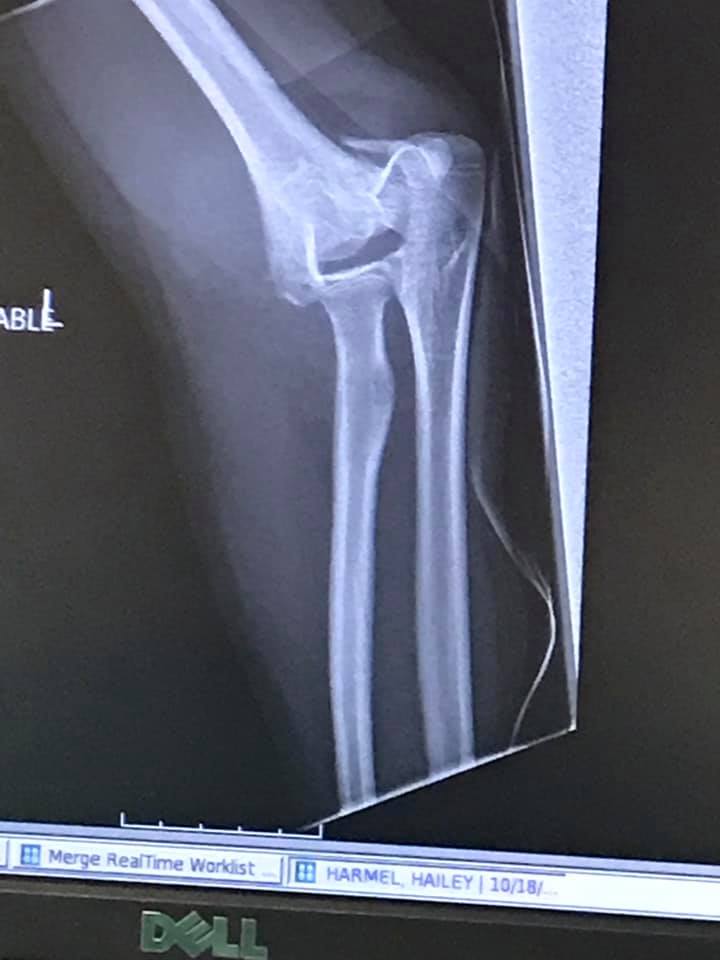

When Hailey got hurt in January after coming off of Buttons she pretty much decided she was finished with riding horses, but especially with showing. Buttons and I made the commitment that we were in this together. I never in a million years thought I was going to lose Buttons before I lost my Annie. I did though! I am still trying to wrap my mind around this. The what if’s I had done this, could I have done more, what did I do wrong? The answers to all of those questions are simple, I did everything I could do. This disease is awful, and it ripped my girl away from me, and threw my heart to the ground in the process.